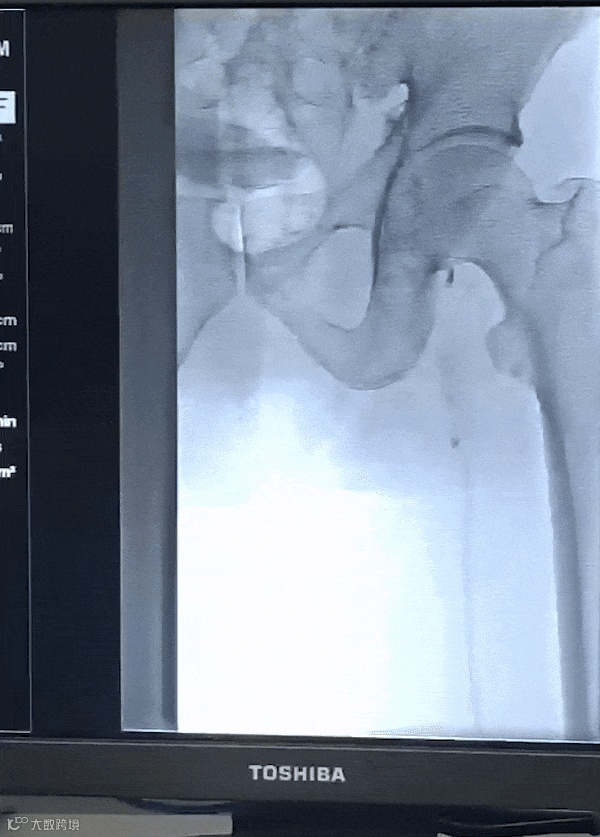

由沈阳市第一人民医院介入科陈建军主任团队运用中天天航™Pro血栓抽吸导管治疗一例急性左下肢深静脉血栓形成且伴有右下肢血流淤滞病变,成功清除血栓并快速恢复肢体灌注,欢迎大家阅读、分享、交流!

手术过程

术后总结